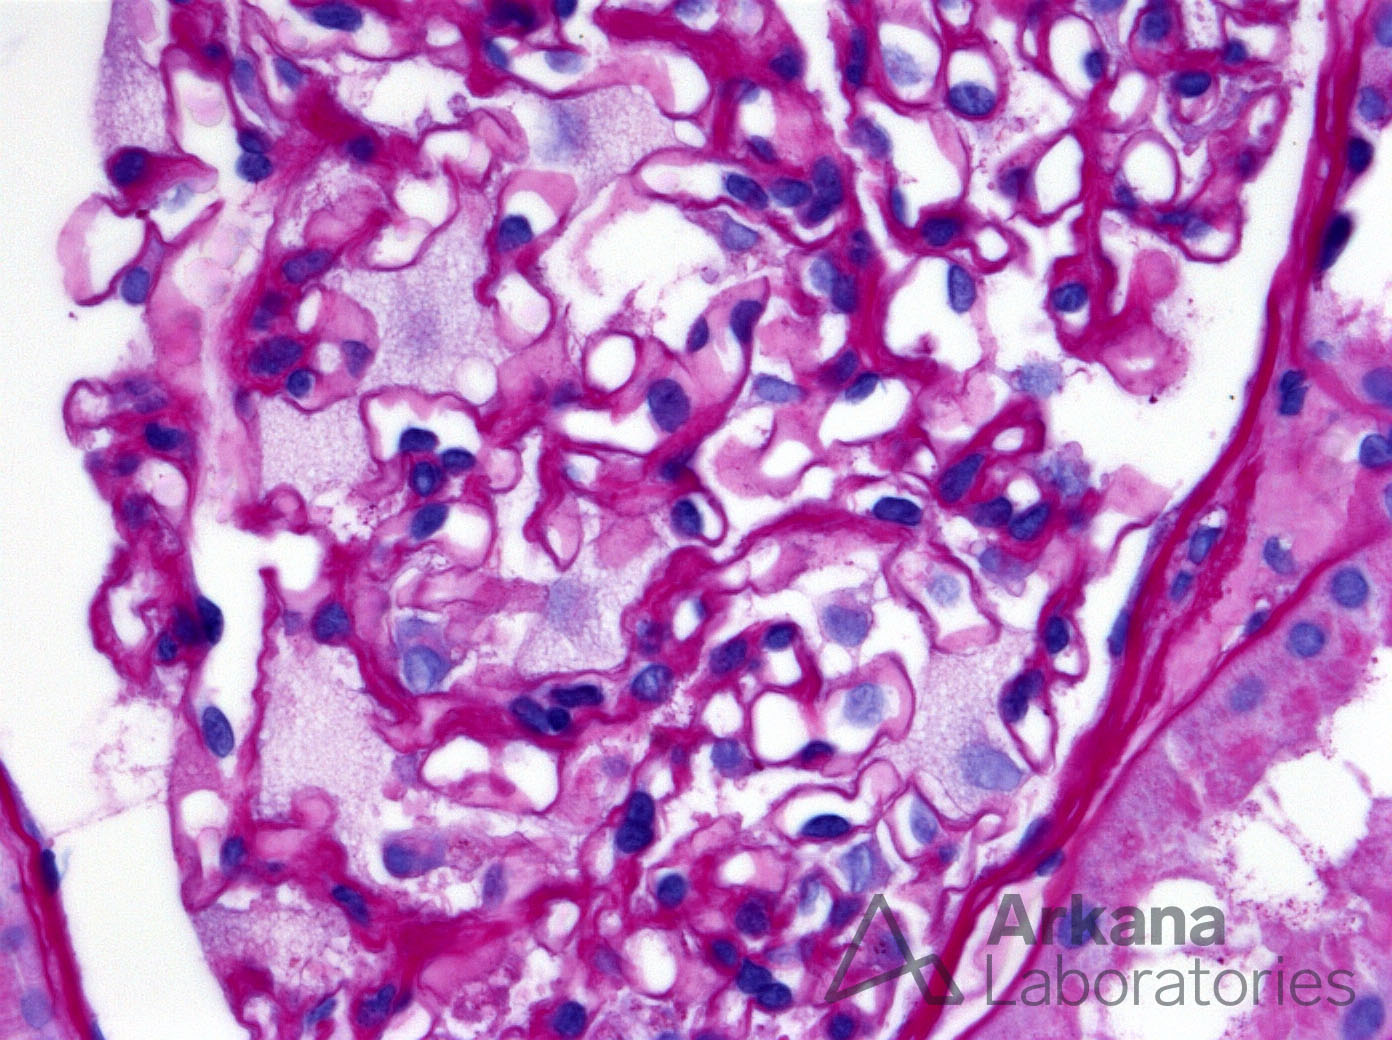

Foamy Podocytes in Fabry Disease